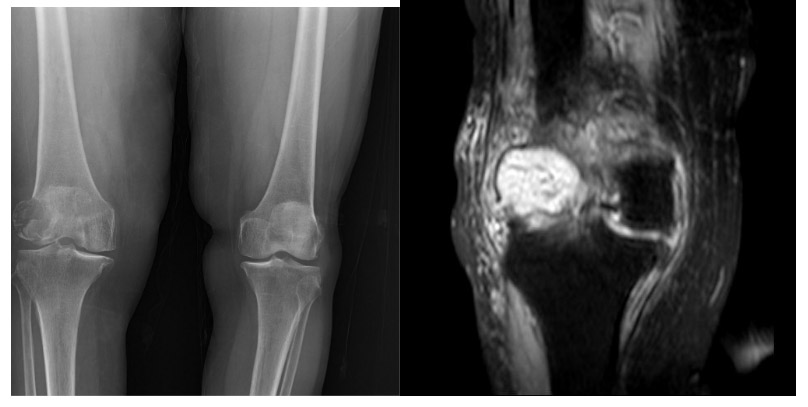

CASE 45: Pathological fracture due to knee (distal femur) metastasis of kidney (renal cell) cancer.

Before the surgery: X-ray shows a lytic lesion and fracture in the lateral aspect of the right distal femur, and MRI shows tumor tissue and widespread edema.